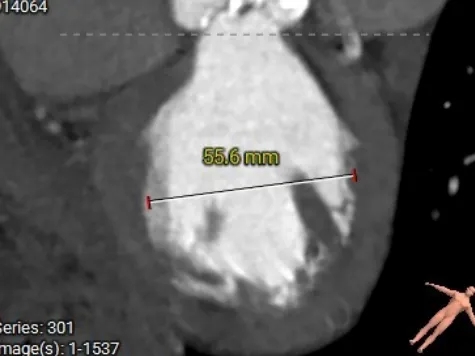

术前CT测量

主动脉根部测量

Annulus 26.2mm

LVOT 26.4mm

钙化积分:1371

SOV

22.6*34.9mm

STJ 31mm

AAO 34.8mm

-

Type0二叶瓣

流出道直筒型

左窦团块状重度钙化,右窦零星钙化

瓣上结构测量

瓣下2mm

26.3mm

瓣上2mm

23.9mm

瓣上4mm

23.3mm

瓣上6mm

22.1mm

瓣上8mm

22.2mm

瓣上10mm

冠脉风险评估

LCA Height

RCA Height

冠脉开口高度可,结合二叶瓣形态,预估冠脉风险相对较低。